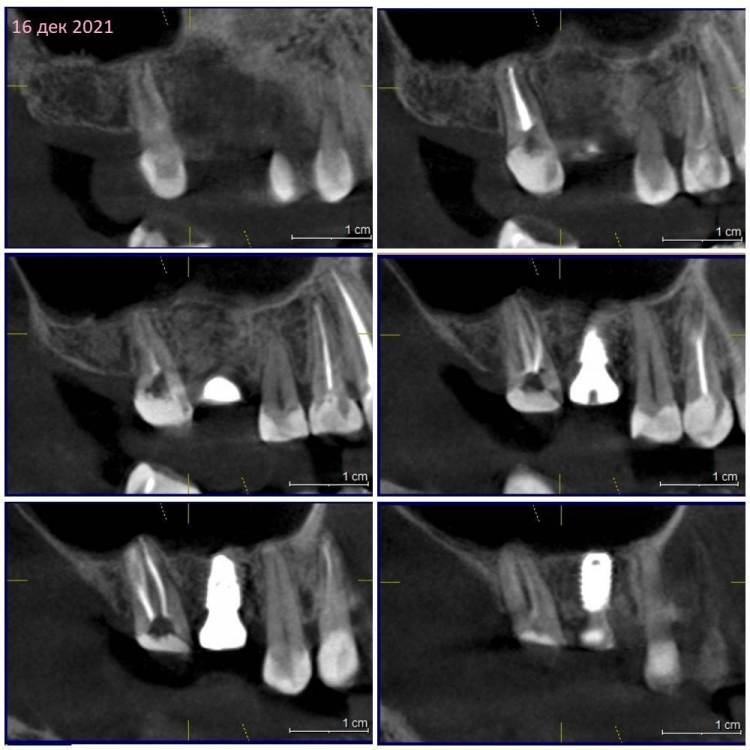

Зуб 17.

Сентябрь 2021 – удалили 16й с одномоментной имплантацией и подсыпкой кости, сразу поставили формирователь.

Недавно с ужасом обнаружила, что 17 сместился в сторону импланта 16, уткнувшись в формирователь(

1. Нормально ли пролечены каналы 17? Стоит ли пытаться еще раз перелечить их все или другие два, кроме небного?

2. Если характер болей изменился после замены соседа на имплант и нет улучшения уже 4 месяца, может ли имплантация быть этому причиной?

3.  Почему так быстро сместился 17 в сторону 16? И помешает ли это при установке коронок на 16, 17?

КТ наскринила парочку. Если нужно будет более подробно – выложу еще.

302205257_3162021.thumb.jpg.18a720cc1985f835a447cc570076ff9a.jpg

409358705_1620212.thumb.jpg.217d1a7f90d9ddcd10fa9fa074c4e53f.jpg

1663100281_1620211.jpg.bf12cf24a1038fe62444cbec72388c0a.jpg

230110228_1620213.thumb.jpg.2a516e39278fed762fb4f254cd64fd77.jpg